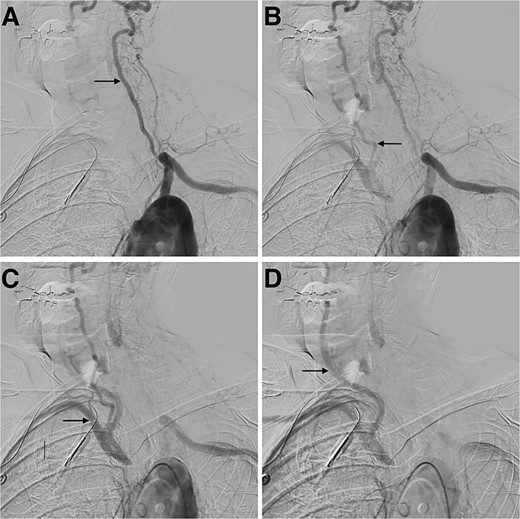

A cerebral angiogram demonstrated left common carotid occlusion (Fig. 1A) and the occlusion of the origin of the right brachycephalic trunk (Fig. 1B). Consequently, the left vertebral artery is the only cerebral vessel from the aortic arch filling anterogradely, resulting in retrograde flow to the brachycephalic trunk and of the right common carotid artery and right vertebral artery (Fig. 2A–D). The left internal carotid artery is filled from the left occipital artery, which is filled by the left vertebral artery. Intracranially the patient has the posterior communicating artery and the anterior communicating artery.

Digital subtraction angiogram demonstrating: (A) anterograde flow in the left vertebral artery and contrast going through the basilar formation. (B) Retrograde flow in the right vertebral artery. (C) Contrast reaching the right subclavian artery. (D) Anterograde flow in the right common carotid artery.